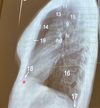

2

3

4

5

Perfectly

Q